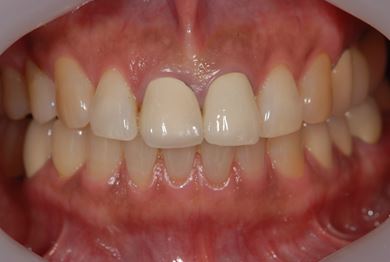

骨再生インプラント治療+セラミック治療+歯肉歯槽骨整形手術

| 性別/年齢 | 女性 / 57歳 | ||||||||||||||||||||||||||||||||

| 主訴 | 左奥上の歯ぐきの痛みの治療相談。 | ||||||||||||||||||||||||||||||||

| 治療内容 | インプラント2本(ソケットリフト、GBR)、メタルボンドセラミッククラウン3本、歯肉歯槽骨整形手術 | ||||||||||||||||||||||||||||||||